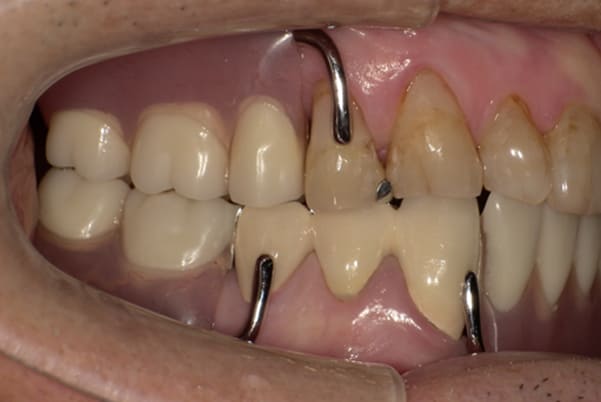

症例レポート[CASE.03]

入れ歯がガタつく、

見た目も改善したい

- 女性(50代)

- 入れ歯がガタつく、何度調整してもよくならない。できれば見た目も良くしたい。

- 上顎精密金属床部分入れ歯

- ジルコニアクラウン3歯

上あごに接する入れ歯に違和感がありになっていたとのことで、プラスチックが大きく削られた入れ歯をされていました。

そのため入れ歯の安定が悪く、お食事の際に入れ歯が動き、がたつきを感じられている状態でした。

前歯にバネにより見た目の問題も抱えておられました。

かみ合わせが低くなった歯を本来の高さに戻し、保険では使用できない歯に負担のかかりずらいバネで、歯の保存、審美性を確保しました。

前歯にバネを設定せず、見えない奥歯に維持力をもたせたバネを用い、またバネのかかる歯の負担軽減を目的に、被せ物は繋げることで強度を増す設計とすることで、入れ歯が動かずガタつき、審美性不良が解消されました。

部分入れ歯と対合歯

入れ歯を修理する中で、入れ歯の上あごの接触面積ではなく、厚みに対しての違和感と診断し、薄い金属を用いた従来の厚みを1/3程度にした入れ歯にすることにより違和感は消失しました。